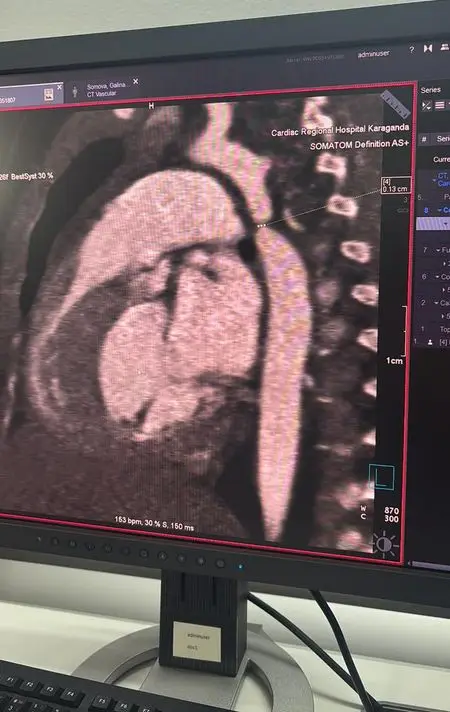

В Караганде в многопрофильной больнице №2, известной как Кардиоцентр, была успешно проведена сложная операция на сердце трёхмесячной девочке, у которой была диагностирована критическая коарктация аорты. Врачи обнаружили данное заболевание во время обследования, когда ребёнка госпитализировали с пневмонией в многопрофильную больницу №1. После выявления патологии, требующей срочного вмешательства, девочку экстренно перевели в Кардиоцентр.

Врачи провели консилиум и приняли решение о проведении операции в рамках мастер-класса с участием ведущих кардиохирургов страны. Из Астаны в Караганду прибыли кардиохирург Галымжан Утегенов и анестезиолог Хафиз Ахмеров. Операция продолжалась почти пять часов и включала резекцию коарктации аорты с наложением анастомоза "конец в конец", что позволило полностью восстановить кровоток.

Во время операции также был выявлен открытый артериальный проток, который был успешно легирован. Галымжан Утегенов отметил, что операция была технически сложной, но прошла в плановом режиме. В настоящее время состояние ребёнка внушает оптимизм, и многое зависит от процесса послеоперационного восстановления.